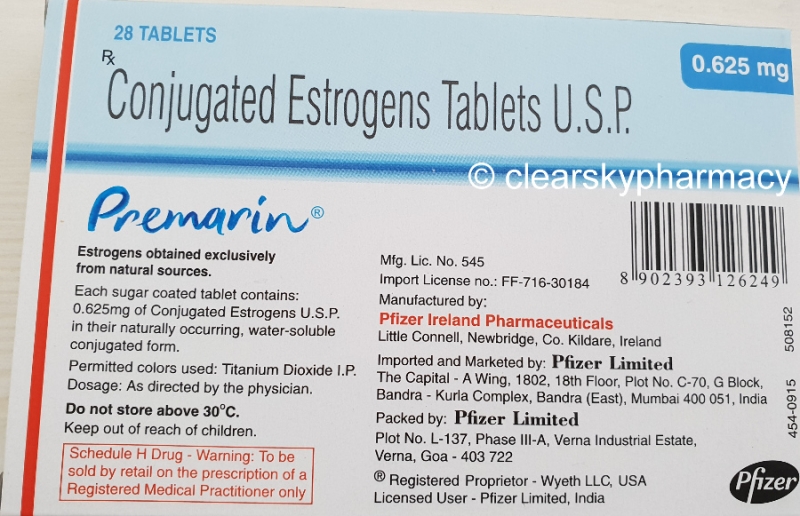

Prescribers should consider using equivalent preparations to those that their patients are currently using. |

Your doctor will want to prescribe you the lowest effective dose. We accept: visa, mastercard. |

Please Note: Patients taking Premarin 0. |